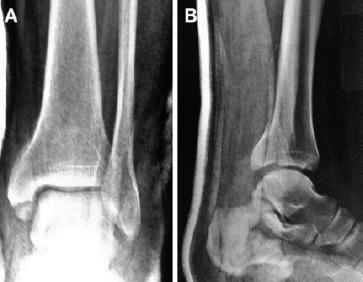

Two cases of trimalleolar fracture-dislocation of the ankle with a double fracture of the medial malleolus are reported. Both of them had a Weber B fracture of the lateral malleolus, accompanied by a posterior dislocation of the ankle and a fracture of the posterior malleolus. The medial malleolus though presented an interesting variation, a large vertical or oblique fragment was combined with a small horizontal fragment of its tip.

报告两例踝关节三踝骨折脱位合并双内踝骨折。两例均为外踝Weber B型骨折,伴有踝关节后脱位及后踝骨折。内踝呈现出一种有趣的变异,一个大的垂直或斜形骨折块与其尖端的一个小的水平骨折块相连。